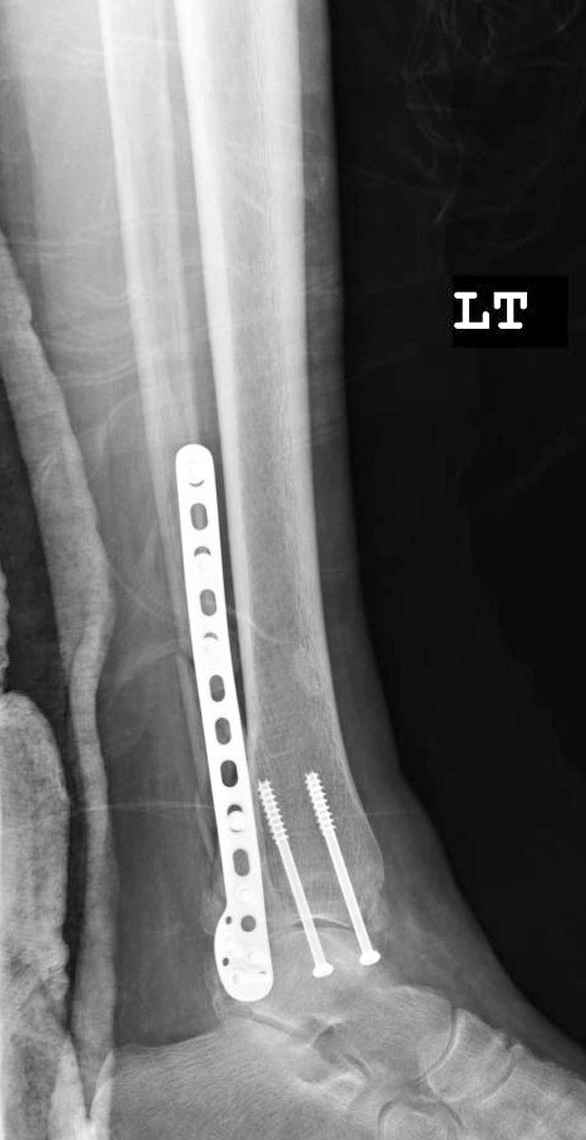

Пока я был в интернатуре, предпочитали осуществлять стабильный остеосинтез с ранней функцией. См. приложения и полнотекстный вариант

статьи.